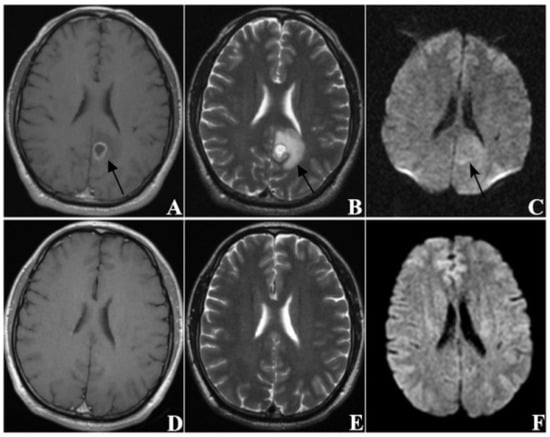

| DWI sequence signal | |

| hyper-intensity | 278 (86.1) |

| iso-intensity or hypo-intensity | 45 (13.9) |

| EI | 2.928 × 10−22 |

| volume > 1801.145 mm3 | 1 | 1.077 | 1.957 × 10−6 |

| EI > 3.835 | 2 | −2.007 | 2.928 × 10−22 |